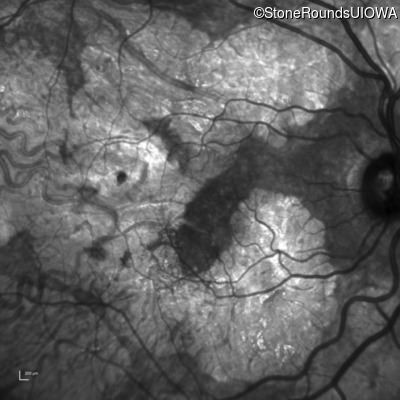

AR Stargardt Disease (IIA)

Age at visit: 51 years

This 51 year old woman first experienced some abnormality in her distance vision when she was 27 years old. She feels that her vision has been stable since that time.

Diagnosis & molecular findings

Disease Gene Allele 1 variant(s) Allele 2 variant(s) Inheritance mode

AR Stargardt Disease ABCA4 Gly1507Arg GGG>AGG IVS42+1 G>A AR